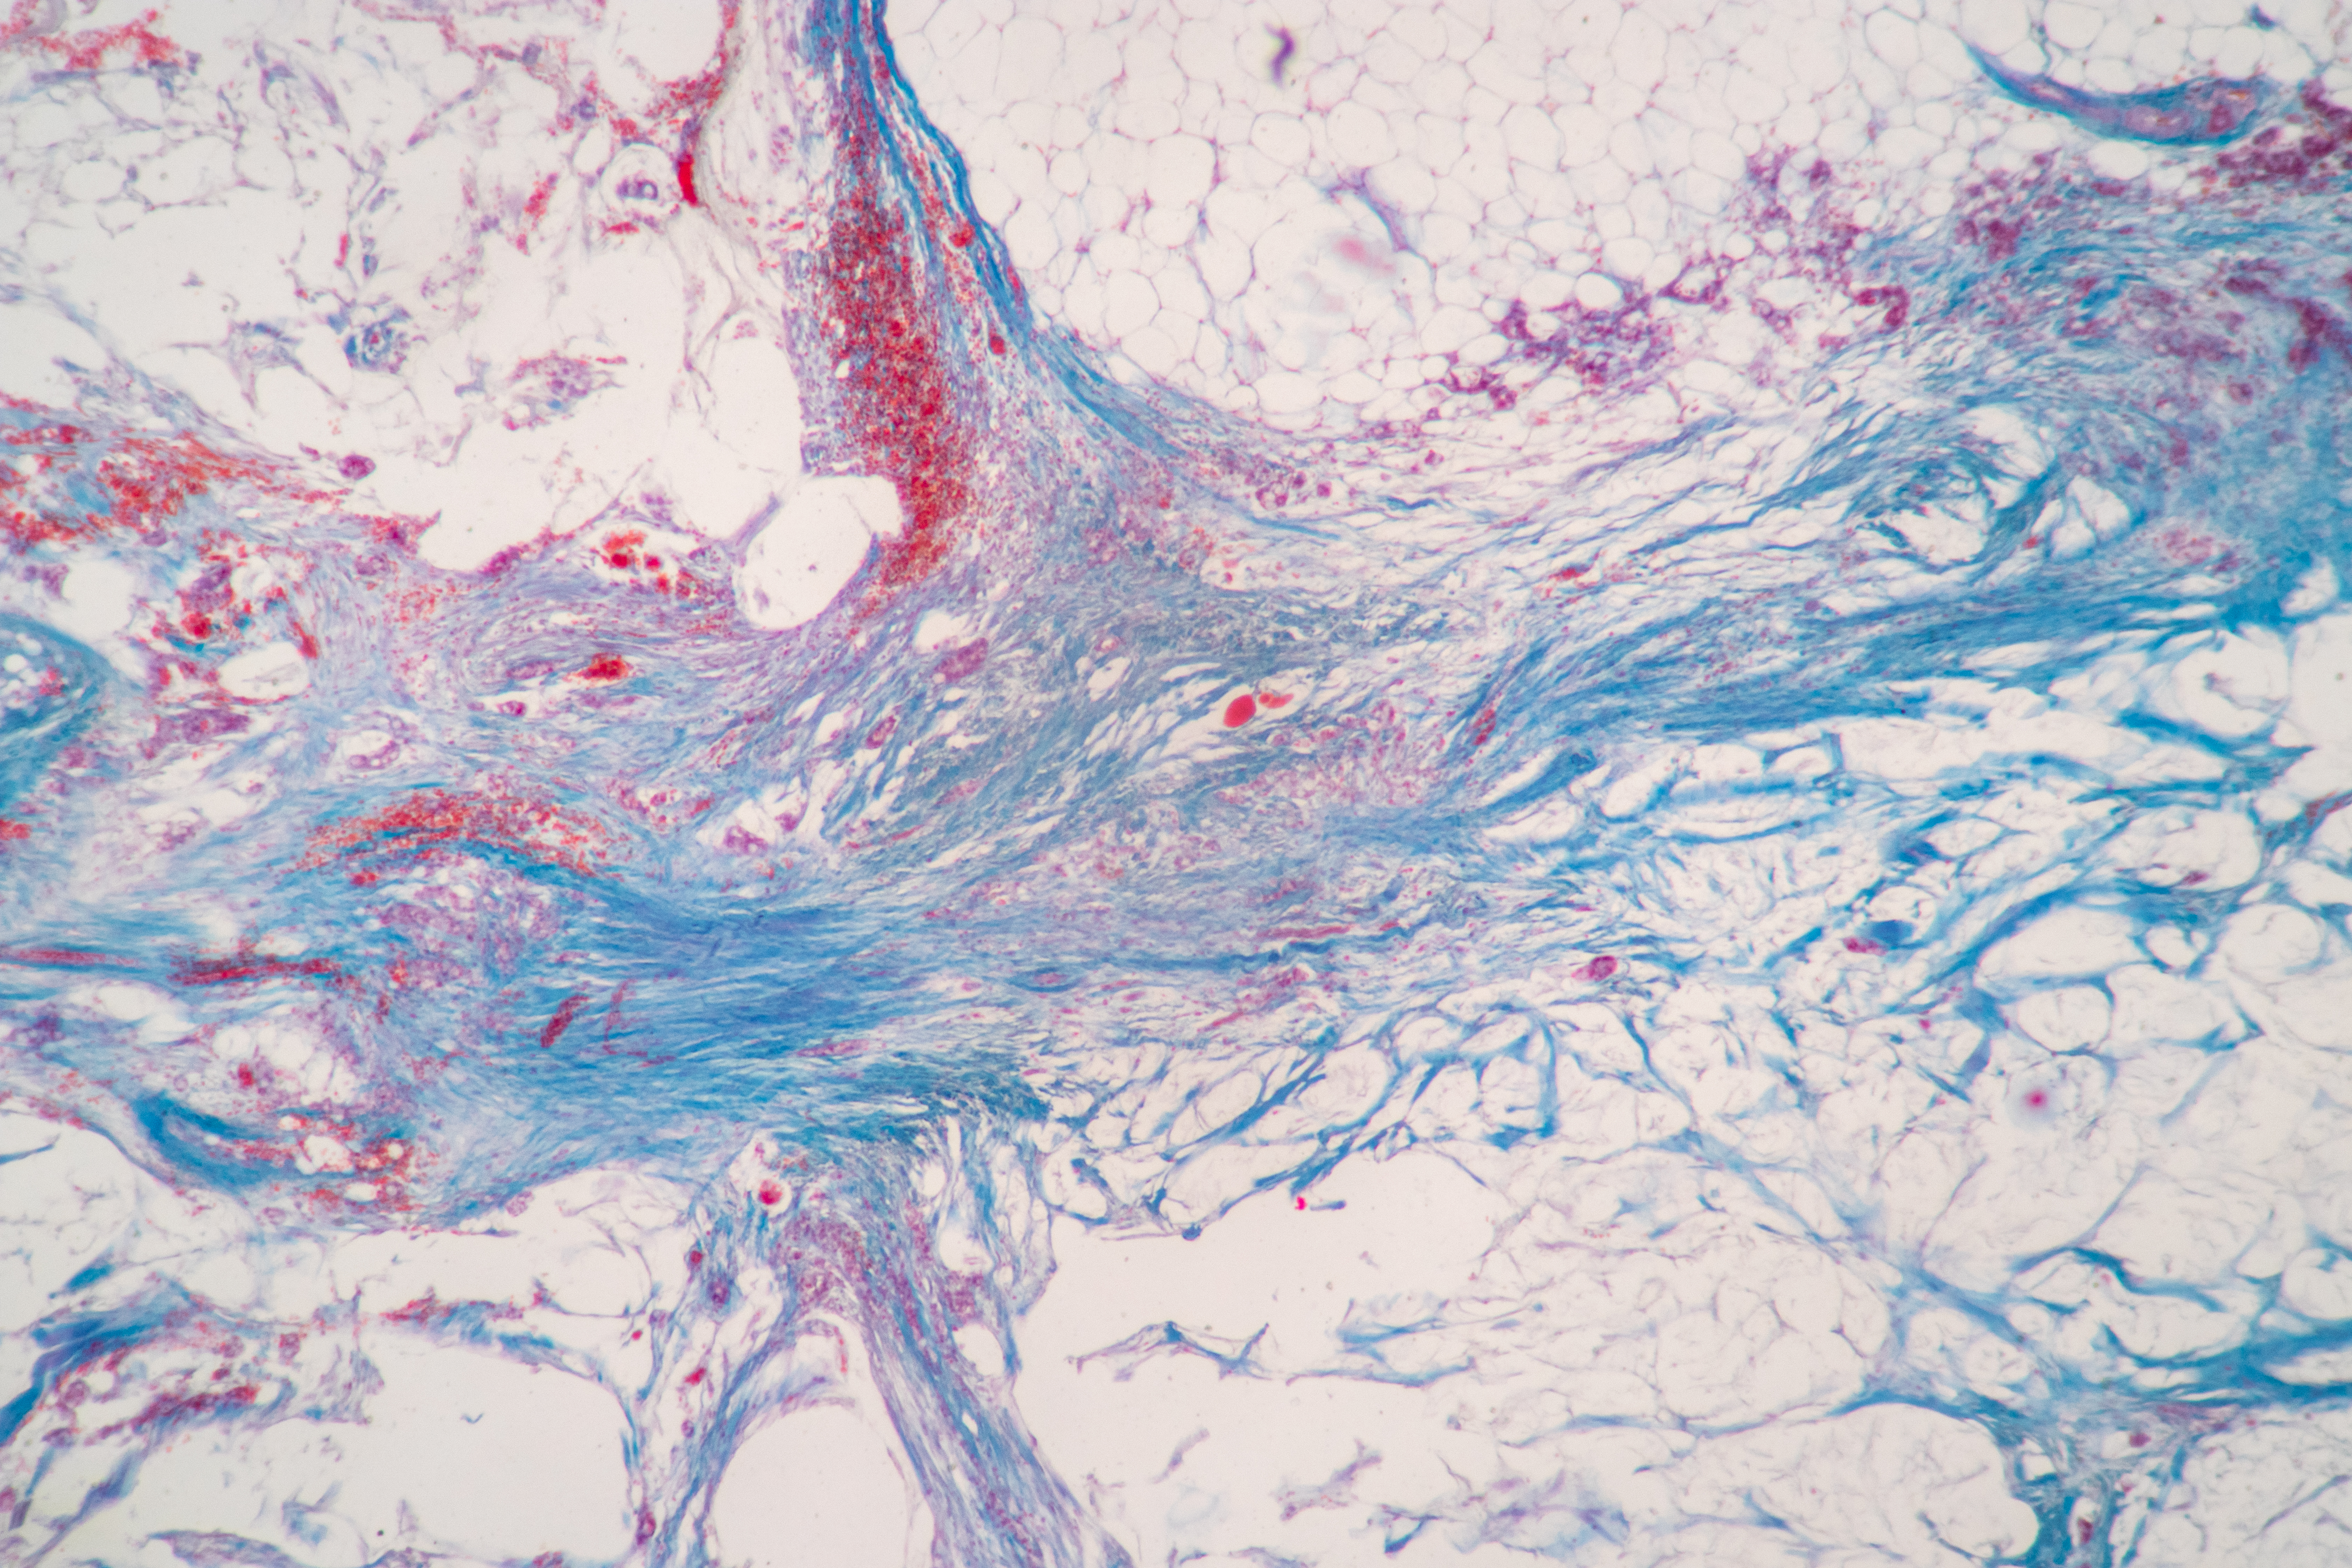

Belumosudil prevents the polymerization of G-actin to F-actin, including the downregulation of MRTF-related profibrotic gene expression.6

↓ Fibrosis

Belumosudil downregulates fibrosis, as demonstrated by decreased collagen deposition around the bronchioles and the delayed progression of scleroderma in animal cGVHD models.3